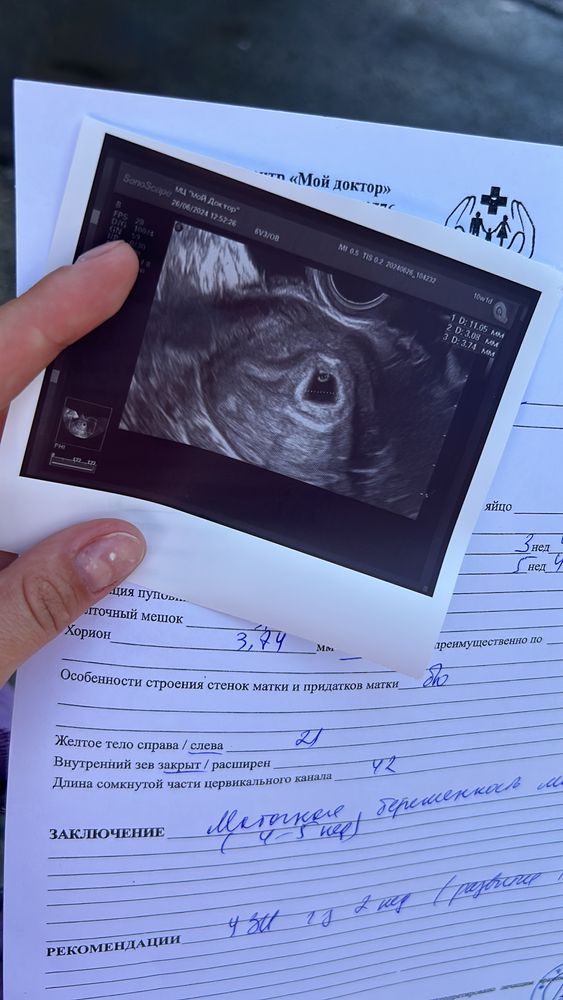

А вот и наша кроха!)

Срок 5+3, есть пя и жм 💞 пдр 23.02.2025

Сегодня была на УЗИ , беременность подтвердили , 4-5недель )))🙏🏻🙏🏻🙏🏻